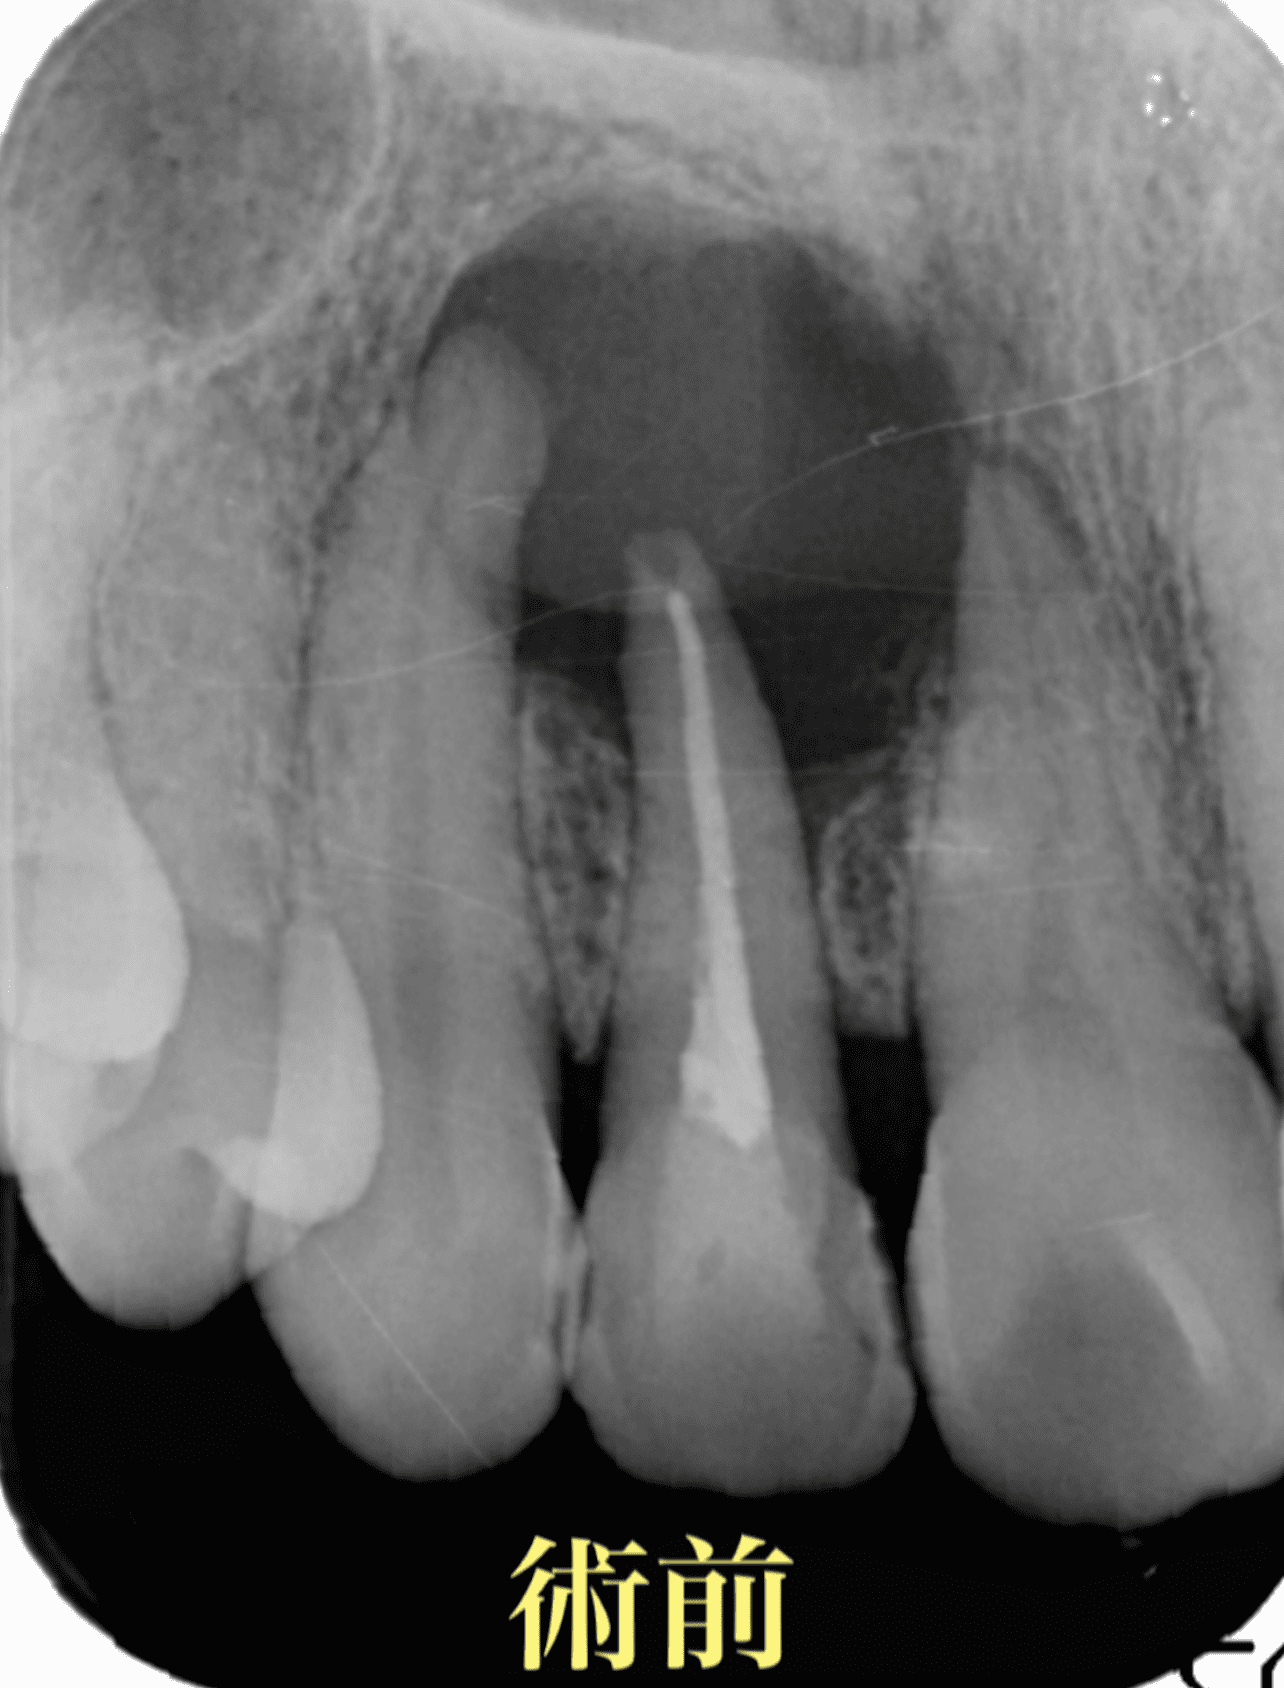

再根管治療8年後の経過

治療前

| 主訴 | 根の先の骨が大きく溶けており抜歯と言われた。何とか残せないか? |

| 診断名 | previously treated Asymptomatic apical periodontitis |

| 治療の方法 | 再根管治療 |